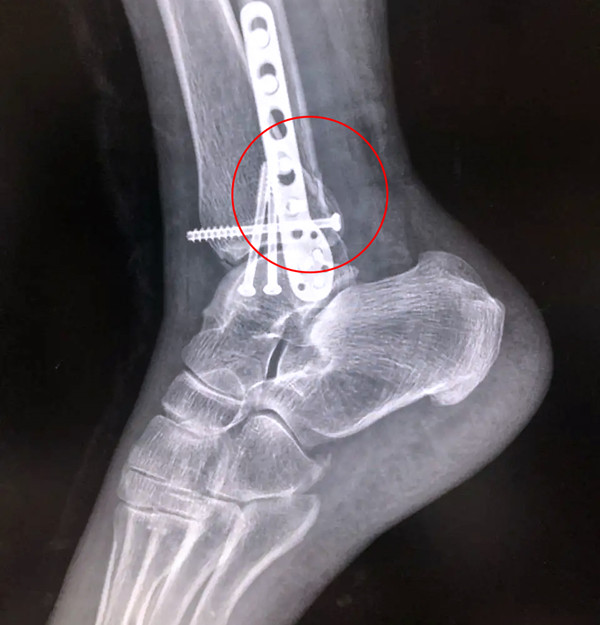

【醫(yī)療科普】Pilon骨折

有一種特殊類型的踝關節(jié)骨折,可能在X影像平片上就不能顯示出來,它就是脛骨的關節(jié)面往里塌陷,我們又稱之為叫“Pilon骨折”。當它往里塌陷后,我們在X影像平片上可能看不出來它是否塌陷,但是我們在CT上可以360°看到踝關節(jié)的影像,這樣就可以看出患者是否存在踝關節(jié)塌陷的骨折。同樣道理,我們在做Pilon骨折手術的時候,普通二維的X影像并不能判斷我們手術復位情況的好壞,這個時候如果醫(yī)生手上有能夠照三維影像的工具,那么對于醫(yī)生的準確手術是非常有好處的。